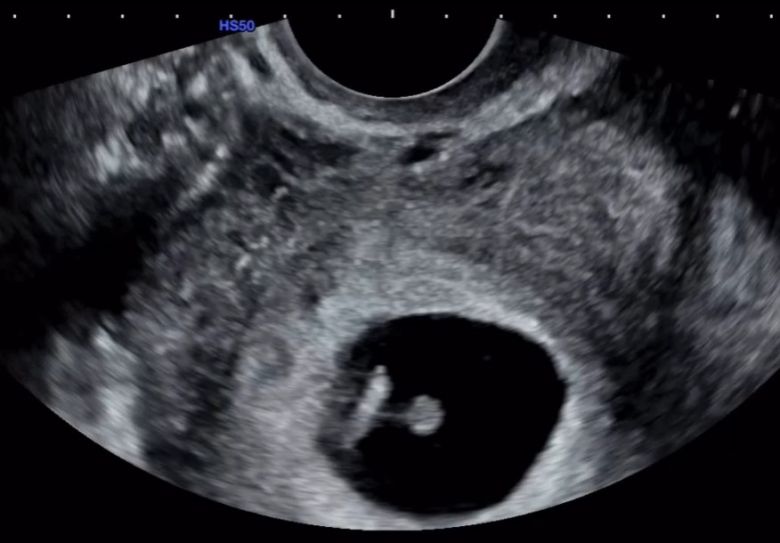

그러면서 "지금 이 순간을 떠올리면, 그 모든 시간들이 이 기적 같은 오늘을 위한 준비였던 것 같다"며 "정말 감사하게도 저를 있는 그대로 온전히 사랑해 주는 사람을 만나게 되었고 그 사랑이 단 한 번에 기적이 됐다"라며 임신 소식을 전했다.